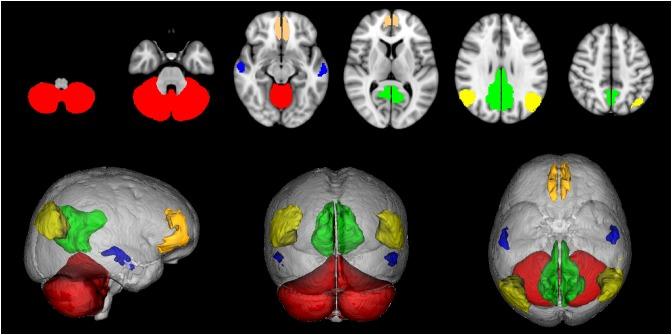

Cognitive impairment affects about 50% of multiple sclerosis (MS) patients, but the mechanisms underlying this remain unclear. The default mode network (DMN) has been linked with cognition, but in MS its role is still poorly understood. Moreover, within an extended DMN network including the cerebellum (CBL-DMN), the contribution of cortico-cerebellar connectivity to MS cognitive performance remains unexplored. The present study investigated associations of DMN and CBL-DMN structural connectivity with cognitive processing speed in MS, in both cognitively impaired (CIMS) and cognitively preserved (CPMS) MS patients. 68 MS patients and 22 healthy controls (HCs) completed a symbol digit modalities test (SDMT) and had 3T brain magnetic resonance imaging (MRI) scans that included a diffusion weighted imaging protocol. DMN and CBL-DMN tracts were reconstructed with probabilistic tractography. These networks (DMN and CBL-DMN) and the cortico-cerebellar tracts alone were modeled using a graph theoretical approach with fractional anisotropy (FA) as the weighting factor. Brain parenchymal fraction (BPF) was also calculated. In CIMS SDMT scores strongly correlated with the FA-weighted global efficiency (GE) of the network [GE(CBL-DMN): ρ = 0.87, = 0.76, < 0.001; GE(DMN): ρ = 0.82, = 0.67, < 0.001; GE(CBL): ρ = 0.80, = 0.64, < 0.001]. In CPMS the correlation between these measures was significantly lower [GE(CBL-DMN): ρ = 0.51, = 0.26, < 0.001; GE(DMN): ρ = 0.48, = 0.23, = 0.001; GE(CBL): ρ = 0.52, = 0.27, < 0.001] and SDMT scores correlated most with BPF (ρ = 0.57, = 0.33, < 0.001). In a multivariable regression model where SDMT was the independent variable, FA-weighted GE was the only significant explanatory variable in CIMS, while in CPMS BPF and expanded disability status scale were significant. No significant correlation was found in HC between SDMT scores, MRI or network measures. DMN structural GE is related to cognitive performance in MS, and results of CBL-DMN suggest that the cerebellum structural connectivity to the DMN plays an important role in information processing speed decline.

认知障碍影响约50%的多发性硬化症(MS)患者,但其潜在机制尚不清楚。默认模式网络(DMN)与认知有关,但在MS中其作用仍知之甚少。此外,在包括小脑的扩展DMN网络(CBL-DMN)中,皮质-小脑连接对MS认知表现的贡献仍未得到探索。本研究调查了DMN和CBL-DMN结构连接与MS患者认知处理速度之间的关联,这些患者既有认知受损的(CIMS),也有认知未受损的(CPMS)。68例MS患者和22名健康对照者(HCs)完成了符号数字模态测试(SDMT),并进行了3T脑磁共振成像(MRI)扫描,其中包括弥散加权成像协议。使用概率纤维束成像重建DMN和CBL-DMN纤维束。这些网络(DMN和CBL-DMN)以及单独的皮质-小脑纤维束使用以分数各向异性(FA)作为加权因子的图论方法进行建模。还计算了脑实质分数(BPF)。在CIMS中,SDMT分数与网络的FA加权全局效率(GE)密切相关[GE(CBL-DMN):ρ = 0.87, = 0.76, < 0.001;GE(DMN):ρ = 0.82, = 0.67, < 0.001;GE(CBL):ρ = 0.80, = 0.64, < 0.001]。在CPMS中,这些指标之间的相关性显著较低[GE(CBL-DMN):ρ = 0.51, = 0.26, < 0.001;GE(DMN):ρ = 0.48, = 0.23, = 0.001;GE(CBL):ρ = 0.52, = 0.27, < 0.001],且SDMT分数与BPF的相关性最高(ρ = 0.57, = 0.33, < 0.001)。在以SDMT为自变量的多变量回归模型中,FA加权GE是CIMS中唯一显著的解释变量,而在CPMS中BPF和扩展残疾状态量表是显著的。在HC中,SDMT分数、MRI或网络指标之间未发现显著相关性。DMN结构GE与MS中的认知表现相关,CBL-DMN的结果表明小脑与DMN的结构连接在信息处理速度下降中起重要作用。